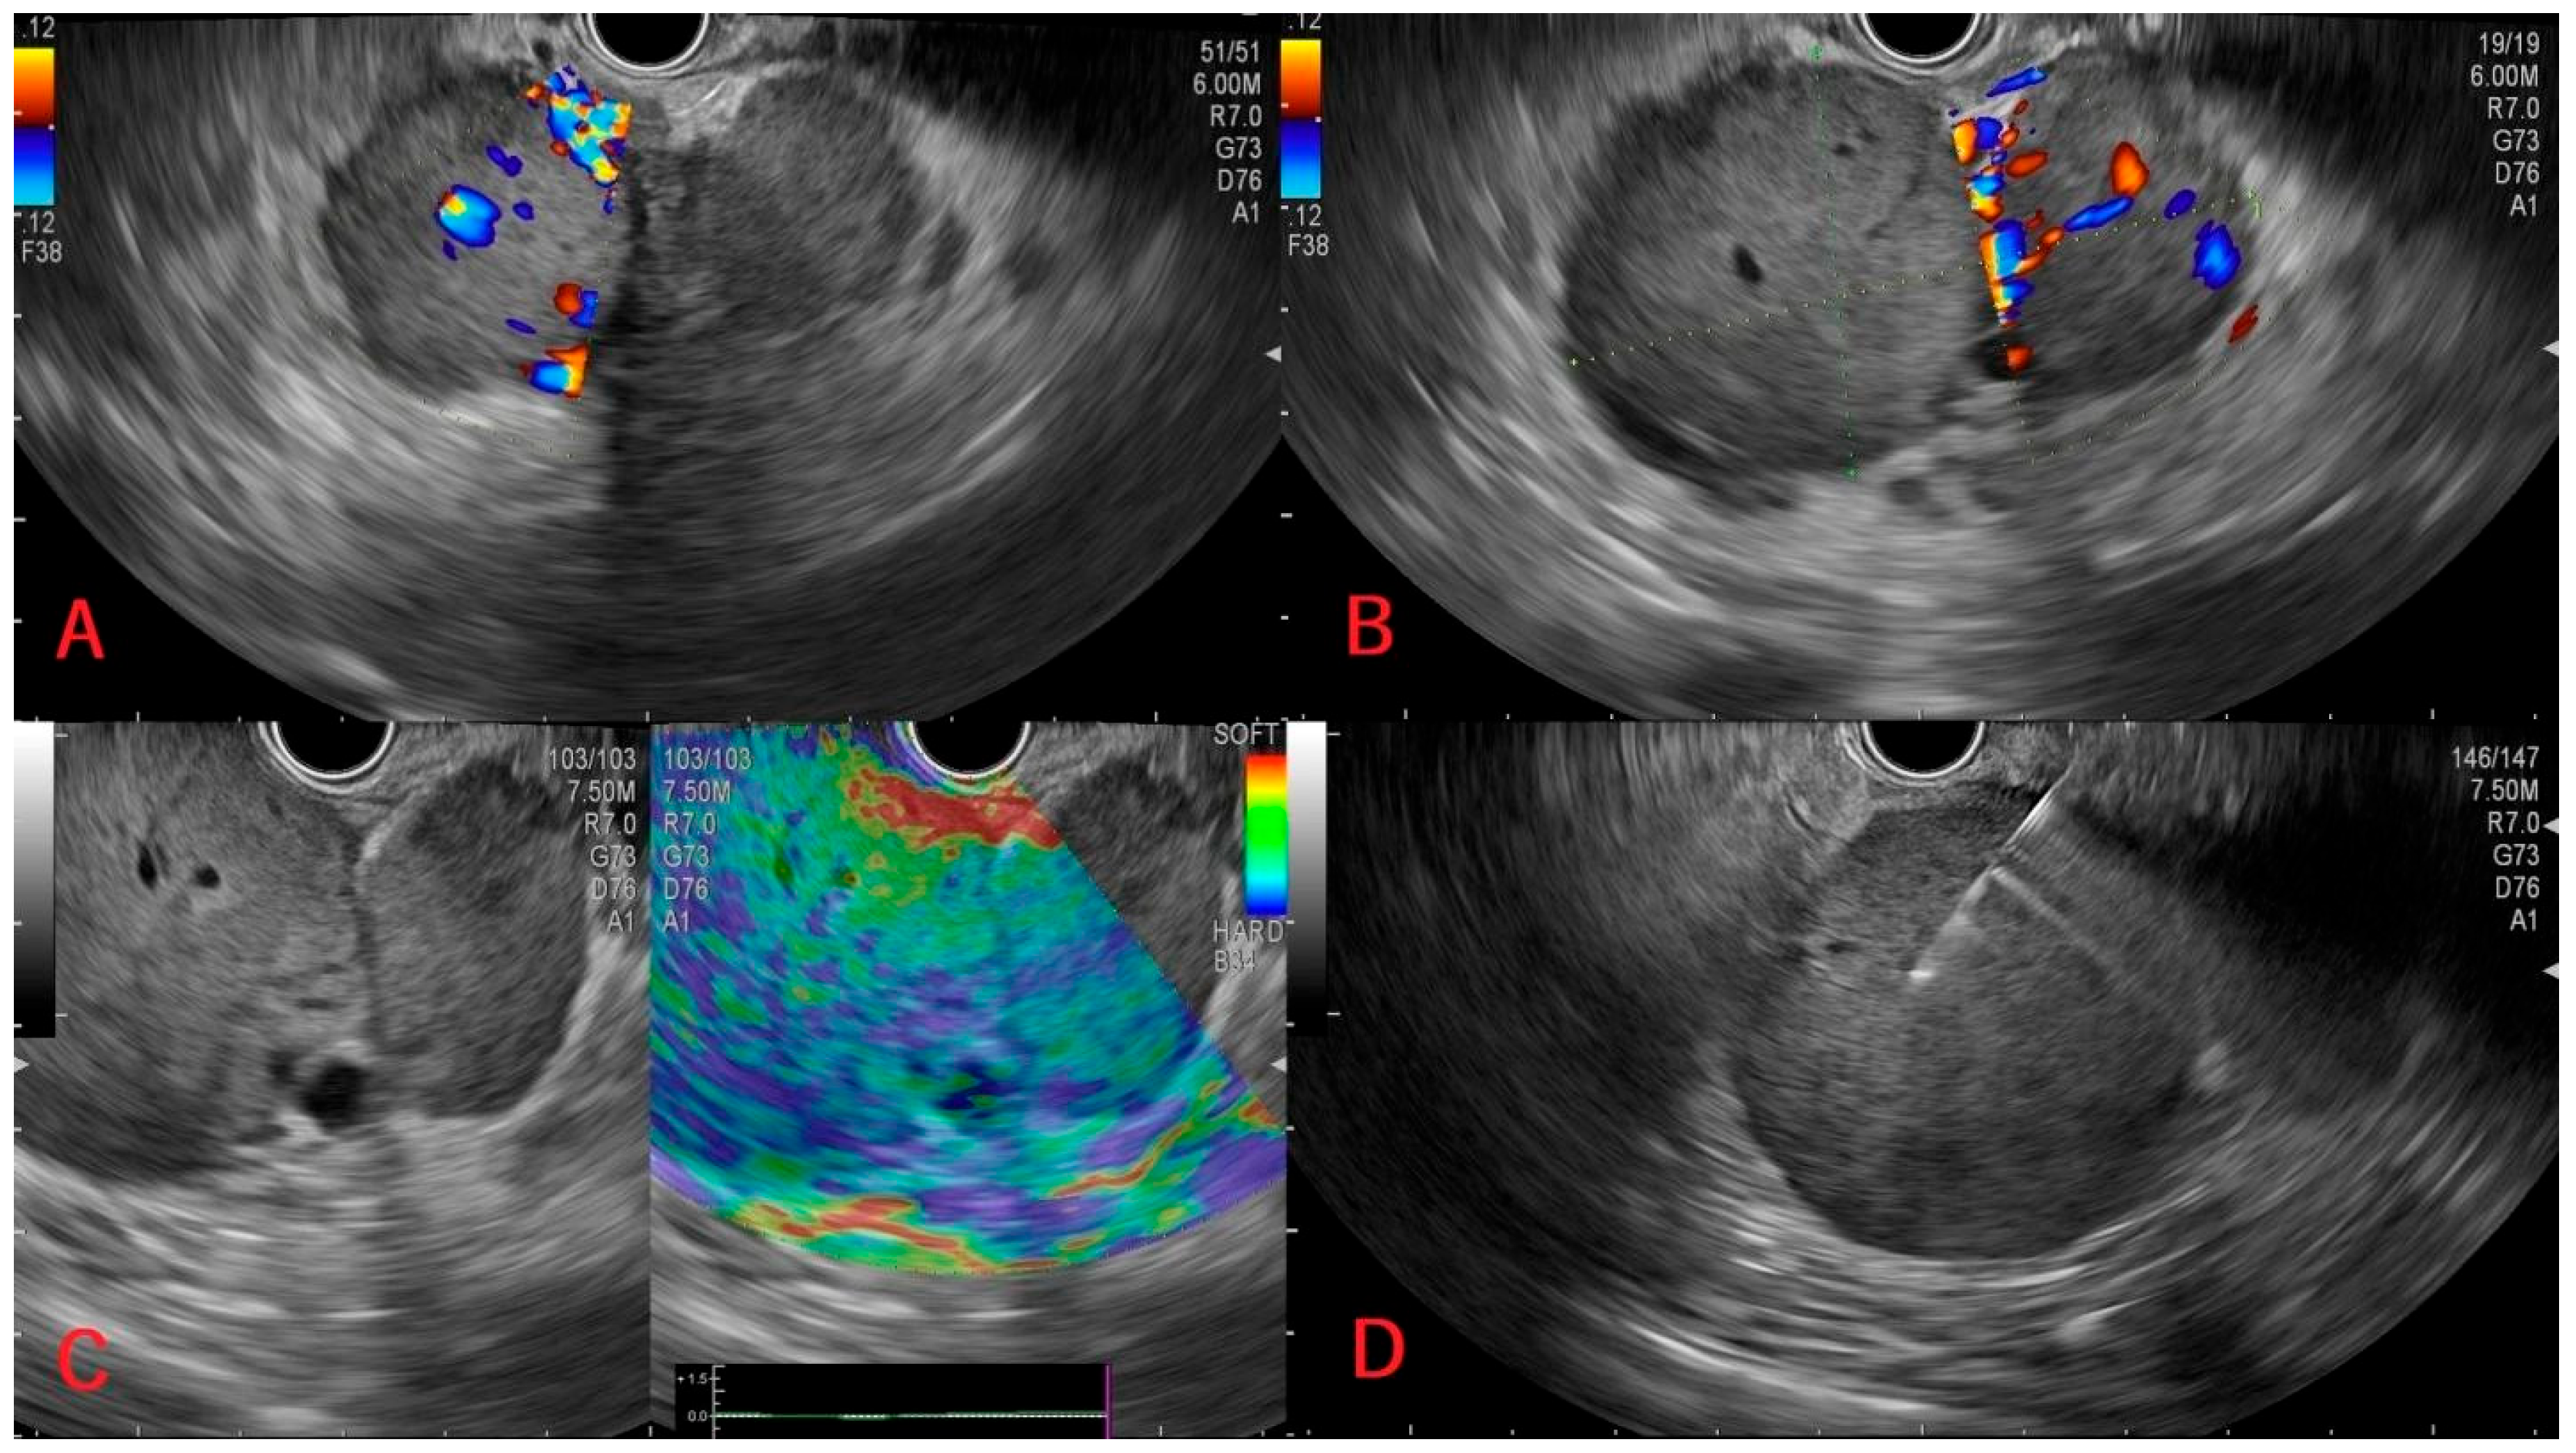

| 2 | 72/M | Known left renal tumor and pulmonary metastases—a caudal pancreatic lesion apparent on CT; cardiovascular comorbidities, cholecystectomy | Cephalic, 30 × 28 mm. | Hypoechoic; normal Doppler signal; hard. | Negative: chromogranin, synaptophysin, CK7, CK20, p63, HSA. Positive: AE1/AE3, PAX8, CAIX. | Perilesional fluid outline ~3 cm, suggestive of de novo hematoma. It did not increase in size and Hb remained normal. | CT→EUS with FNA→Oncologic treatment only (advanced stage). Unknown follow-up data. |

| 3 | 61/F | Referred for painless jaundice and mild pruritus. CT: small renal tumor, cephalo-pancreatic lesion, lung/liver metastases. No significant medical history. | Uncinate process; bilobed; 68 × 41 mm. | Hypoechoic, rich Doppler signal; predominantly hard consistency. | Negative: chromogranin, synaptophysin, CK7, CD10, AE1/AE3. Positive: Ki-67 (5–10%), PAX8 CAIX. | No significant short-term complication. | CT→EUS with FNA→Oncologic treatment only (advanced stage); cardiac arrest during hospitalization. |